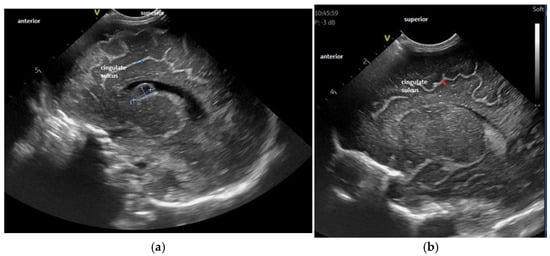

- The gyral maturation pattern—evaluated in 3 sections—coronal at the level of the foramen of Moro—looking at the Sylvian fissure and the depth of the sulci: sagittal—looking at the frontal gyri and sulci and the presence of the central/marginal sulcus and parasagittal, temporal, at the level of the insula [39]. The cortical gyral maturation was assessed according to previously published scores [15,20], and to know patterns of sulcal and gyral maturation [21,22], divided into three categories: